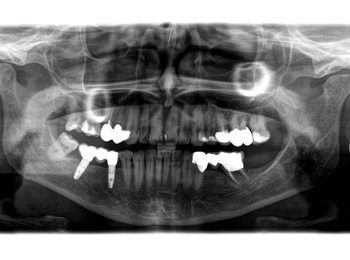

OPG Zustand nach Vorbehandlung und Freilegung der Implantate.